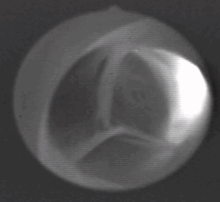

مقطع عرضي للصمام الأبهري، يُظهر الشرف الثلاث منغلقة، كما يُظهر مخرج الشريان التاجي الأيسر فقط.